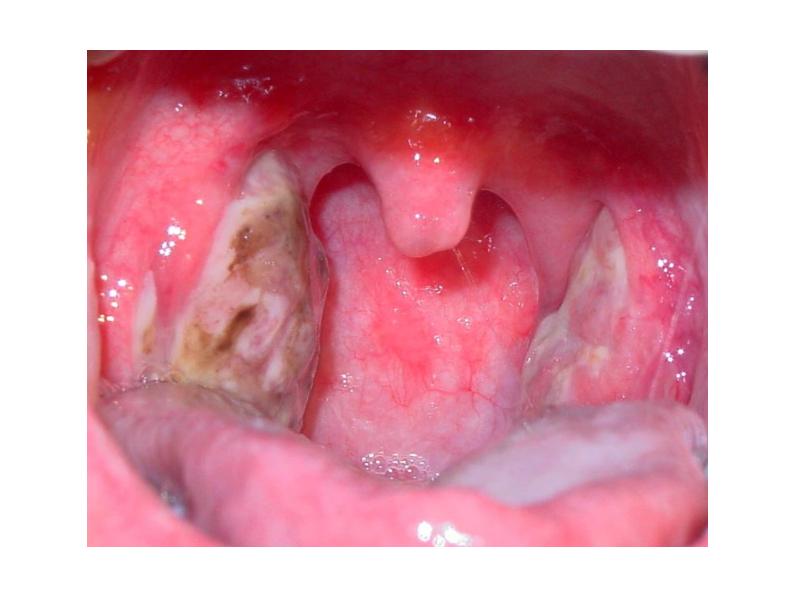

- 22. Флегмонозная ангина (интратонзиллярный абсцесс) Флегмонозная ангина встречается относительно редко. Ее развитие